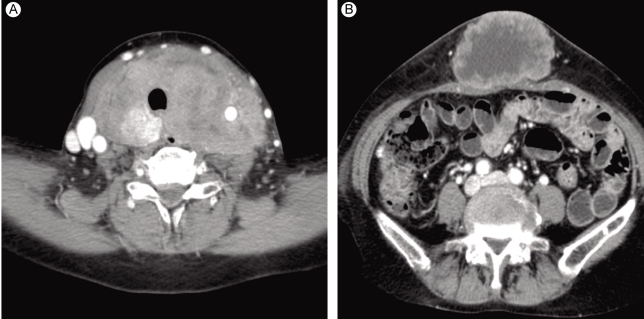

Figure 2

Computed tomography revealed a huge thyroid mass (A) and a cutaneous mass in the umbilical area (B).

A 63-year-old female was admitted to our hospital for the evaluation of a huge abdominal mass. One month earlier, when the patient first perceived the abdominal mass, it measured about 2 cm. Recently, a neck mass also increased rapidly in size, with accompanying dysphagia, shortness of breath, and hoarseness. She had no history of goiter. On physical examination, she had a resting tachycardia with a pulse rate of 100-110 per minute. The abdominal mass was about 15 cm in diameter (Fig. 1A). A huge, firm neck mass occupied both lobes of the thyroid, with palpable lymph nodes on the left (Fig. 1B). She also had a 3-cm skin nodule on her right thigh that was hard and non-tender (Fig. 1C). Computed tomography (CT) revealed huge thyroid (Fig. 2A) and periumbilical (Fig. 2B) masses, infiltrating adjacent tissues. The abdominal mass was based primarily in the subcutaneous fat layer. A pulmonary mass, suggestive of metastasis, was also detected by CT. There was no definite evidence of bone metastasis on a bone scan. The initial thyroid function tests were consistent with a hyperthyroid state: thyroid stimulating hormone (TSH) < 0.11 mU/L (normal range, 0.4 to 4.1); free T4 (fT4) 3.34 ng/dL (normal range, 0.70 to 1.80); thyroglobulin 171.8 ng/mL (normal range, 0 to 40); and thyroglobulin antibody 85 U/mL (normal range, 0 to 100 U/mL). Anti-thyroglobulin antibody, anti-thyroid peroxidase antibody, and serum calcitonin were all normal.